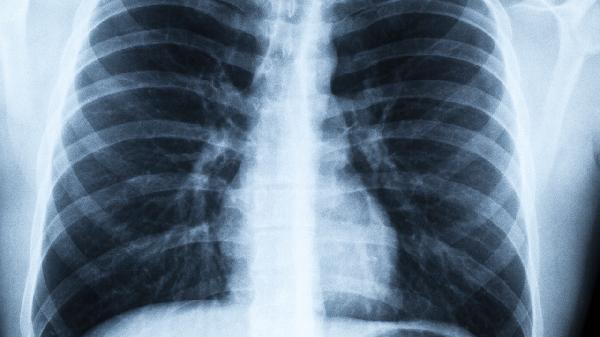

甲型和乙型流感病毒是成人病毒性肺炎的常見(jiàn)病因。病毒通過(guò)血凝素蛋白與呼吸道上皮細(xì)胞結(jié)合,導(dǎo)致細(xì)胞壞死和炎癥反應(yīng)。臨床特征包括突發(fā)高熱、肌痛等全身癥狀,胸部CT可見(jiàn)多肺葉磨玻璃影。糖尿病患者和孕婦感染后易出現(xiàn)急性呼吸窘迫綜合征。

除SARS-CoV-2外,229E、OC43等冠狀病毒也可引起肺炎。病毒通過(guò)血管緊張素轉(zhuǎn)換酶2受體侵入細(xì)胞,病理特征為肺泡透明膜形成。老年患者常見(jiàn)淋巴細(xì)胞減少和D-二聚體升高,部分病例需機(jī)械通氣支持。